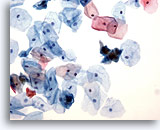

Miction, résultat négatif

La miction représente le moyen le rapide plus rapide d’obtenir un échantillon d’urine.

20x

Miction, résultat négatif

La miction représente le moyen le rapide plus rapide d’obtenir un échantillon d’urine.

20x